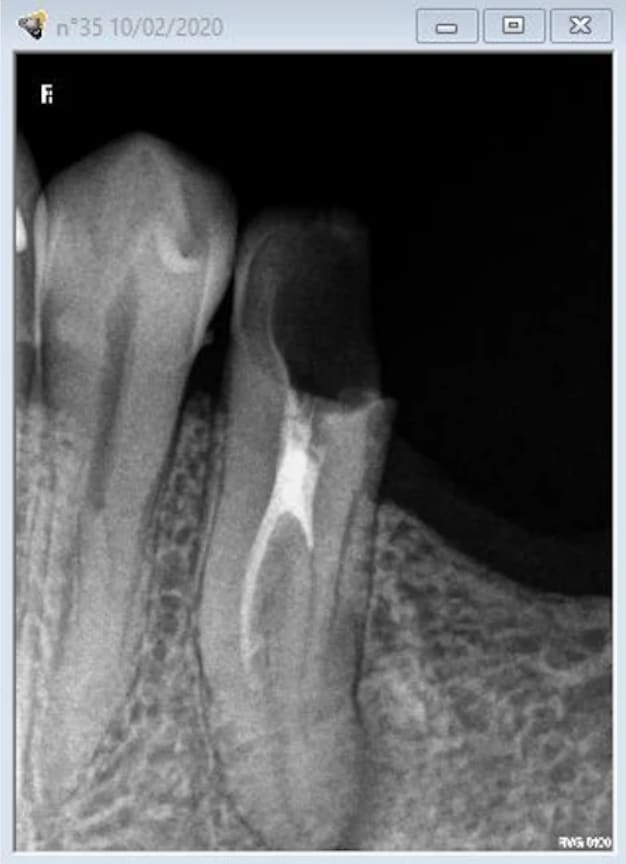

J'ai besoin de votre avis face à cette situation.

Je dénombre au moins 3 apex sur la rétro.

L'endo se tente ? Si oui comment ?

Très atypique, en effet!!

Ca me parait ingérable, sauf à être très délabrant pour l'accès, et donc se retrouver avec une racine inexploitable!

De mémoire, j'avais du négocier ça au protaper, en élargissant largement l'entrée commune, mais surtout sans descendre jusqu'à la pseudo furcation pour ne pas foirer les entrées.

L'obturation avait été compliquée, je pense que j'avais du mettre un cone en place, couper à la furcation, mettre le second en place, couper à nouveau, mettre le troisième, et mc spadden dans le bordel.

Si tu es certain de la vitalité canalaire (mais vu la radio ça m'étonnerait), un protocole type pulpo basse serait une bonne alternative.

Aucun souci pour traiter ces vraissemblablement 3 canaux. C’est un métier !))

Par le passé j'ai déja traité avec succès des canines biradiculées. Avec une furcation plus haute et moins abrupte.

Mais là ca dépasse mes compétences.

Dommage, ça se tente, en général un canal lingual qui descend tout seul, et deux vestibulaires un peu plus cotons à passer, mais là sur ta radio, ils sont bien visualisables, et l'angulation entrée canalaire/chambre n'est pas à 90°. Un beau challenge.